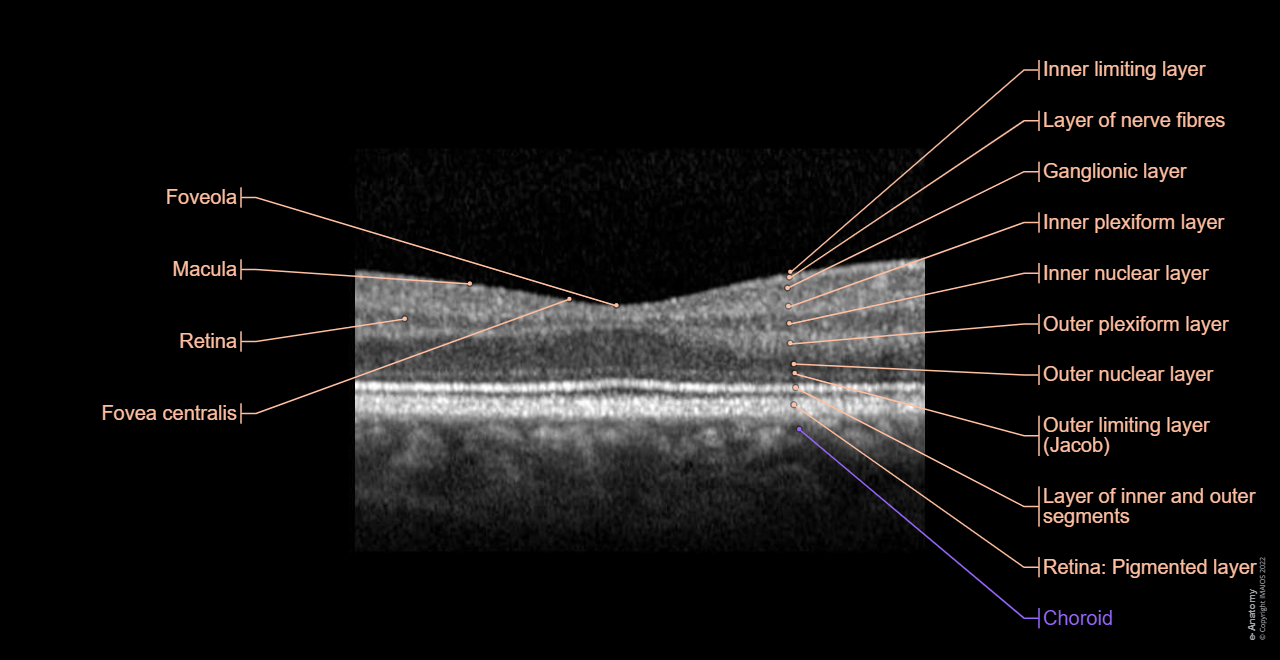

Optical coherence tomography (OCT): Retina, Layer of inner and outer segments, Outer limiting layer, External limiting membrane, Outer nuclear layer, Outer plexiform layer, Inner nuclear layer, Inner plexiform layer, Ganglionic layer, Layer of nerve fibres, Inner limiting layer

Optical coherence tomography (OCT)